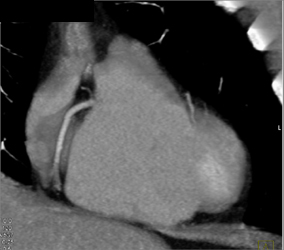

Normal Coronary Arteries